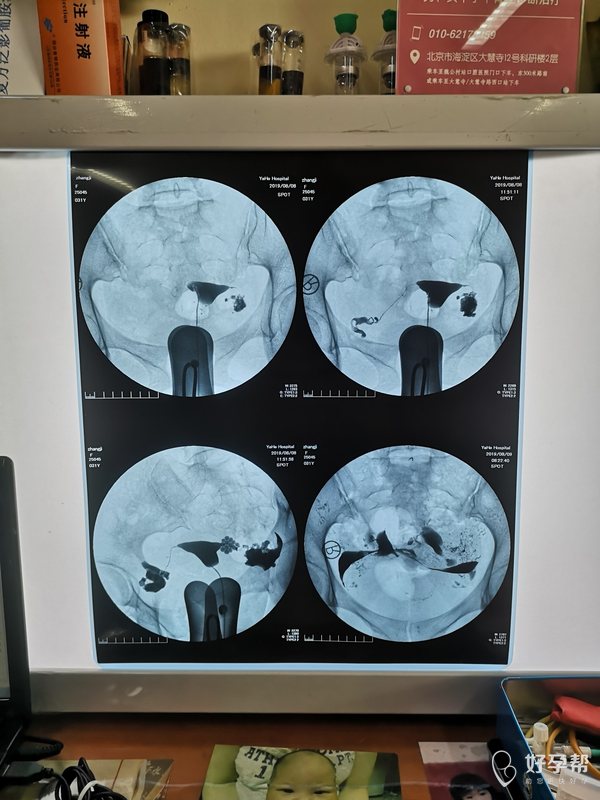

今年31岁,做过宫腹腔联合镜,两侧都有积水,

今年31岁,做过宫腹腔联合镜,两侧都有积水,术中处理了积水 也做了造口整形,半年后又去复查了输卵管造影,又过去了半年还是没怀上,是不是我该去做试管了?手术做了一年了我需要再去做二次手术吗?需要结扎或者切除输卵管吗?

建议直接试管了,如果积水没有再长就不需要再手术治疗。不需要结扎或者切除输卵管手术。